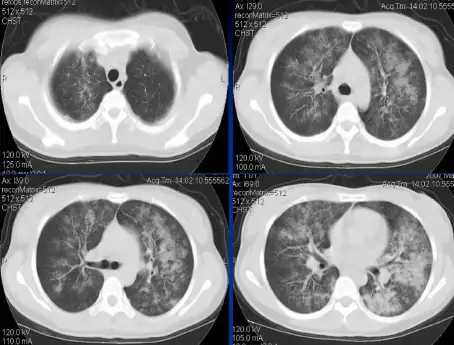

病例:男,33岁,急性肾衰肺水肿。CT表现:①肺间质性肺水肿:两肺血管束增多、增粗,边缘模糊;②肺泡性肺水肿:两肺透光度减低,并见广泛性分布结节样、斑片样密度增高影及毛玻璃样影,边缘模糊,以两肺内、中带分布较明显,形成典型“蝶翼征”;③胸腔积液。